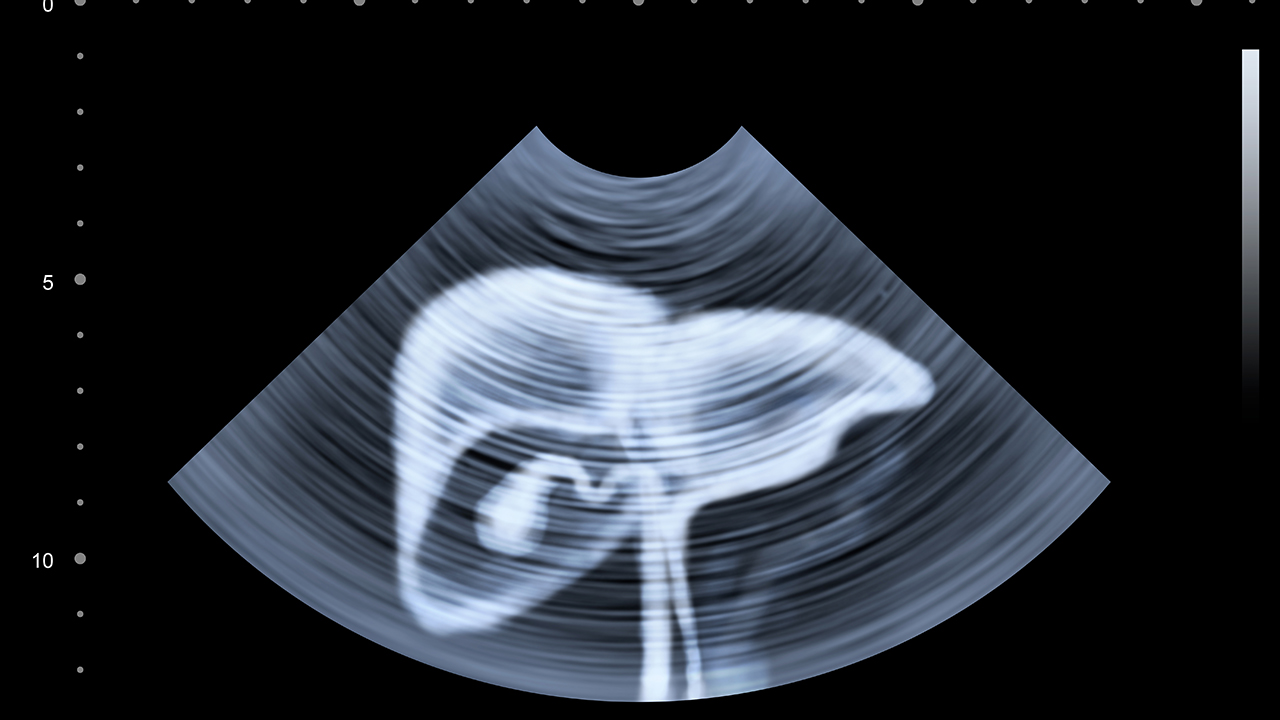

肝癌作为常见的恶性肿瘤之一,其发病与慢性肝炎病毒感染、肝硬化、黄曲霉毒素暴露等因素密切相关。早期诊断和规范治疗对改善患者预后至关重要。

肝癌预防需从控制危险因素入手,乙肝疫苗接种、规范抗病毒治疗可有效降低肝炎-肝硬化-肝癌三部曲风险。避免食用霉变食物,限制酒精摄入,定期体检特别是高危人群每6个月进行肝脏超声和AFP检测。确诊患者应保持良好心态,遵循医嘱规范治疗,注意营养支持,适当运动增强免疫力。治疗后的定期随访对早期发现复发转移至关重要,一般建议术后2年内每3个月复查一次。